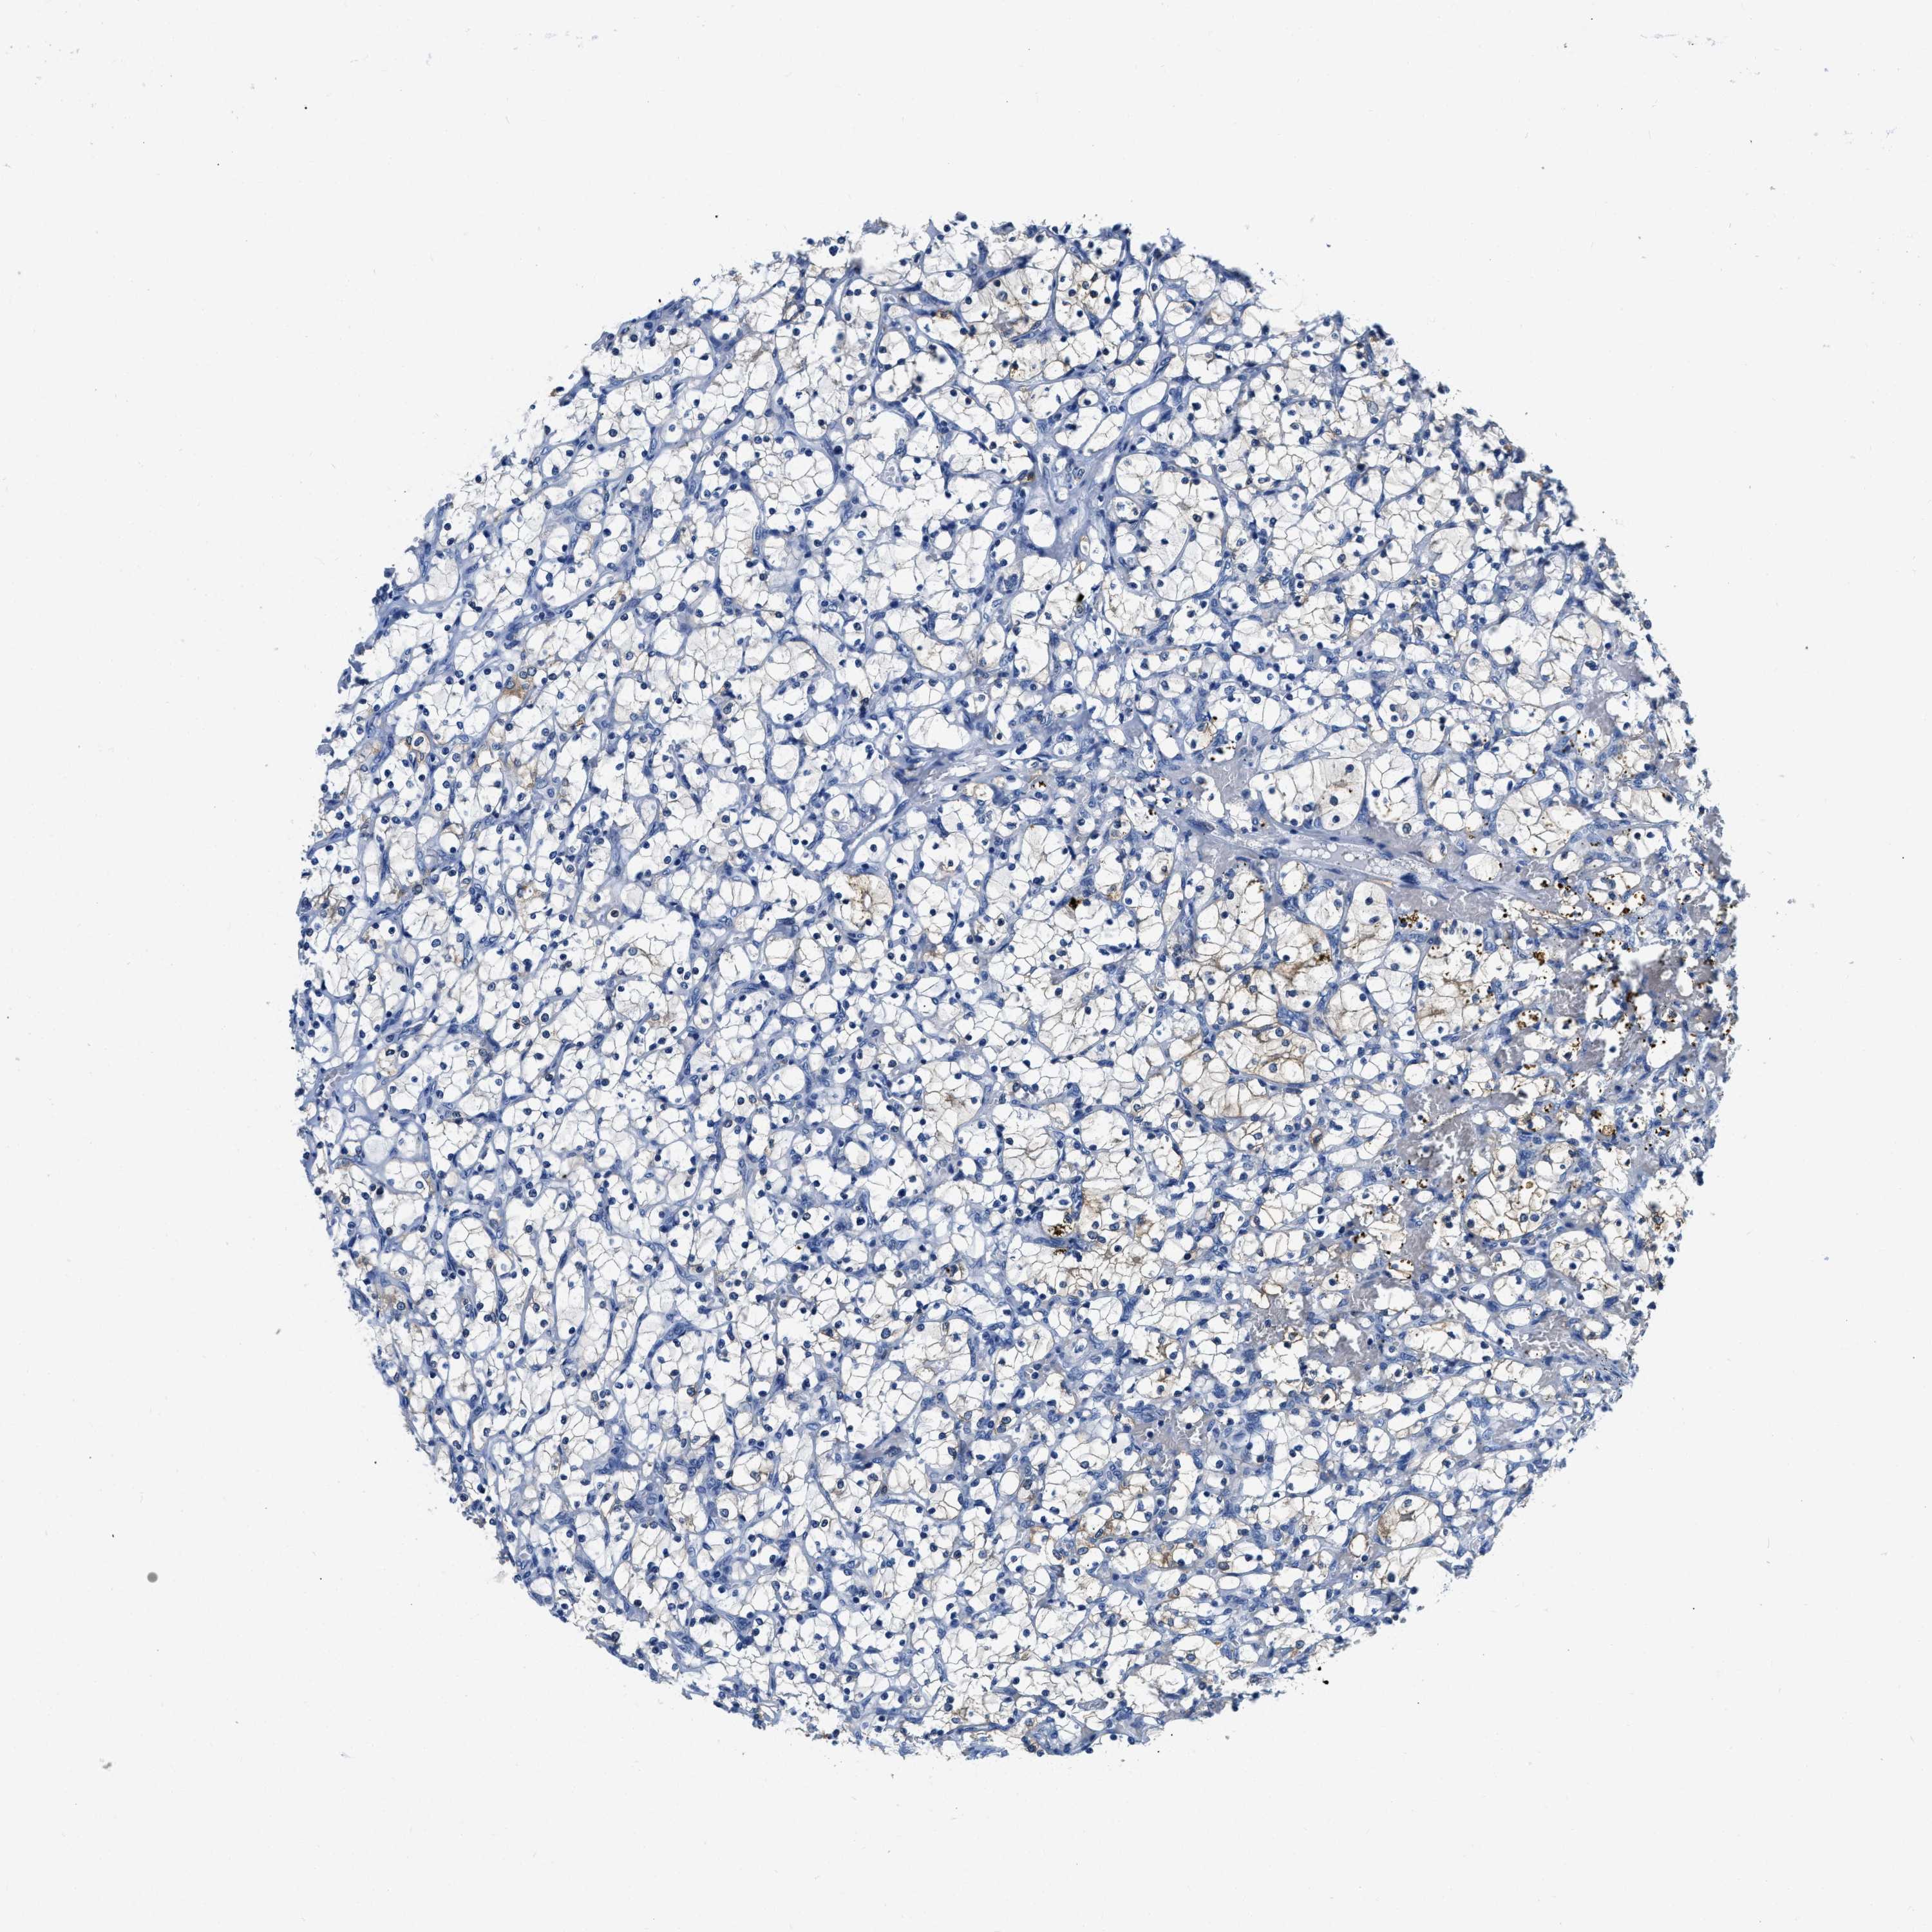

CANCER RENAL CANCER Show tissue menu

KICH TCGA KIRC TCGA KIRC VALIDATION KIRP TCGA PROTEIN RCC CPTAC PROTEIN EXPRESSION

KIDNEY CHROMOPHOBE (TCGA) - Interactive survival scatter ploti

The Survival Scatter plot shows the clinical status (i.e. dead or alive) for all individuals in the patient cohort, based on the same data that underlies the corresponding Kaplan-Meier plots. Patients that are alive at last time for follow-up are shown in blue and patients who have died during the study are shown in red.

The x-axis shows the expression levels (FPKM) of the investigated gene in the tumor tissue at the time of diagnosis. The y-axis shows the follow-up time after diagnosis (years). Both axes are complimented with kernel density curves demonstrating the data density over the axes. The top density plot shows the expression levels (FPKM) distribution among dead (red) and alive patients (blue). The right density plot shows the data density of the survived years of dead patients with high and low expression levels respectively, stratified using the cutoff indicated by the vertical dashed line through the Survival Scatter plot. This cutoff is automatically defined based on the FPKM cutoff that minimizes the p-score. The cutoff can be changed by dragging the vertical line or by entering a cutoff value in the square labeled "Current cut-off".

Under the Survival Scatter plot the p-score landscape (black curve; left axis) is shown together with dead median separation (red curve; right axis). Dead median separation is the difference in median mRNA expression between patients who have died with high and low expression, respectively. It is calculated as follows: median FPKM expression of dead patients with high expression - median FPKM expression of dead patients with low expression. This is intended to aid the user in visually exploring custom cutoffs and the associated p-scores and dead median separation.

Individual patient data is displayed and can be filtered by clicking on one or more of the category buttons on the top of the page. Categories describing expression level and patient information include: high, low, alive, dead, female, male and tumor stages. The scale of the x-axis can be toggled between linear and log-scale by clicking on the "x log" button. Mouse-over function shows TCGA ID, patient information and mRNA expression (FPKM) for each patient.

& Survival analysisi

Kaplan-Meier plots summarize results from analysis of correlation between mRNA expression level and patient survival. Patients were divided based on level of expression into one of the two groups "low" (under cut off) or "high" (over cut off). X-axis shows time for survival (years) and y-axis shows the probability of survival, where 1.0 corresponds to 100 percent.

ZDHHC13 is not prognostic in Kidney Chromophobe (TCGA)